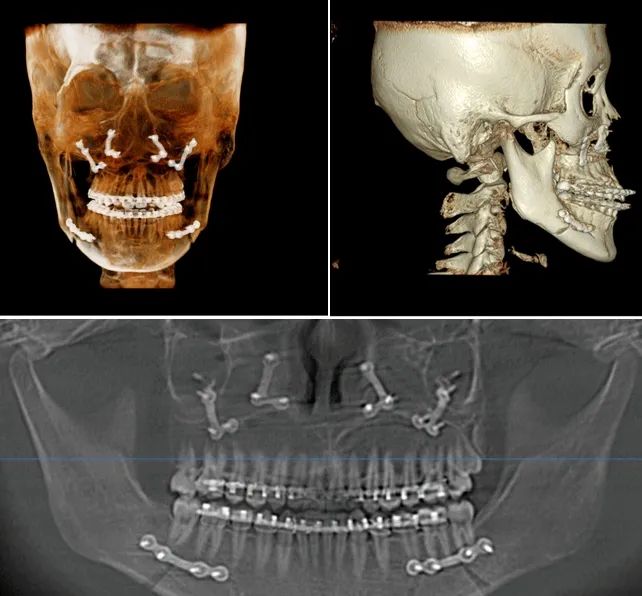

2023年1月,22岁女生因“ 安氏III类错颌畸形 ”入院治疗,口腔科团队为其将上下颌骨切断,完成截骨,后将上下颌骨移动到新位置,并用”钛板“固定,且未伤及面部皮肤。

△下颌升支矢状劈开后退术+上颌骨LefortI型高位截骨术